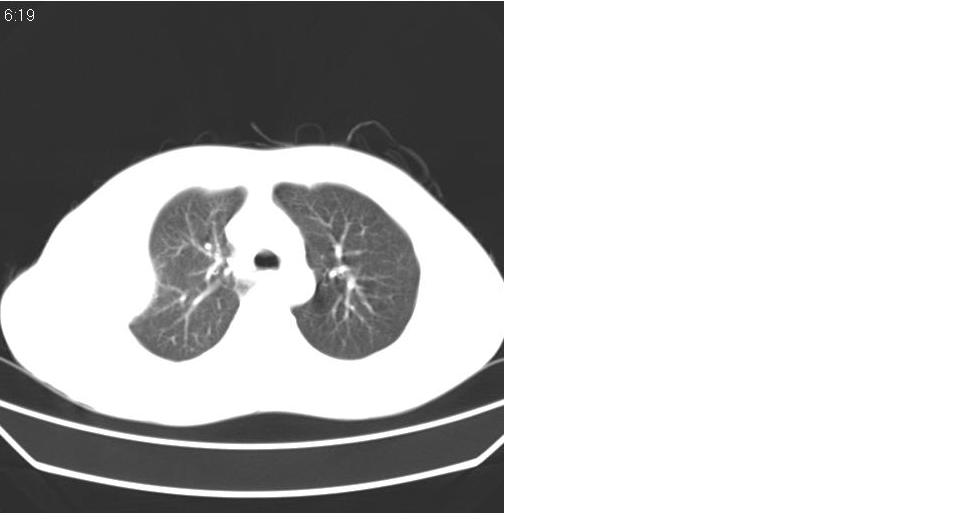

男 21岁,胸闷。

右侧包裹性积液(结核性可能大)。

右侧胸腔积液,部分呈垂滴状,包裹了,最常见的原因是结核引起的